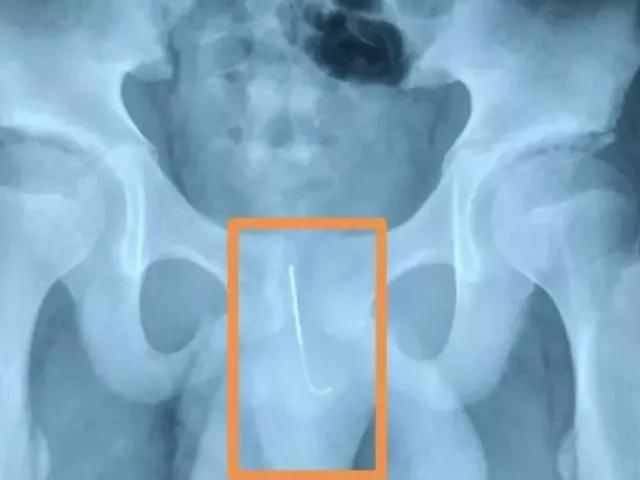

据悉,通过孩子的“骨盆平片”可以明显看到,下腹部有一个尖锐物体,尖头朝下,别说孩子家长,连医生看到这个片子,也不禁捏了一把汗!

南通海安市人民医院消化内科主任医师表示:我们接到电话,说有个小孩贪玩把飞镖从肛门放进去。这个情况一定要紧急处理,如果时间长了或者小孩运动了以后,这个飞镖一端是尖的,而且尖端朝下,正好朝向运动的方向,容易引起小肠穿孔出血或者感染。